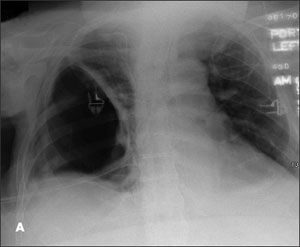

A 50-year-old woman presents to the emergency department with severe dizziness, weakness, and dyspnea of 1 week’s duration. Ten days earlier, an upper respiratory tract infection (URTI) was diagnosed; over-the-counter cough syrup and acetaminophen were prescribed. However, the patient’s condition has steadily deteriorated since then. In addition, her urine has darkened over the past few days.